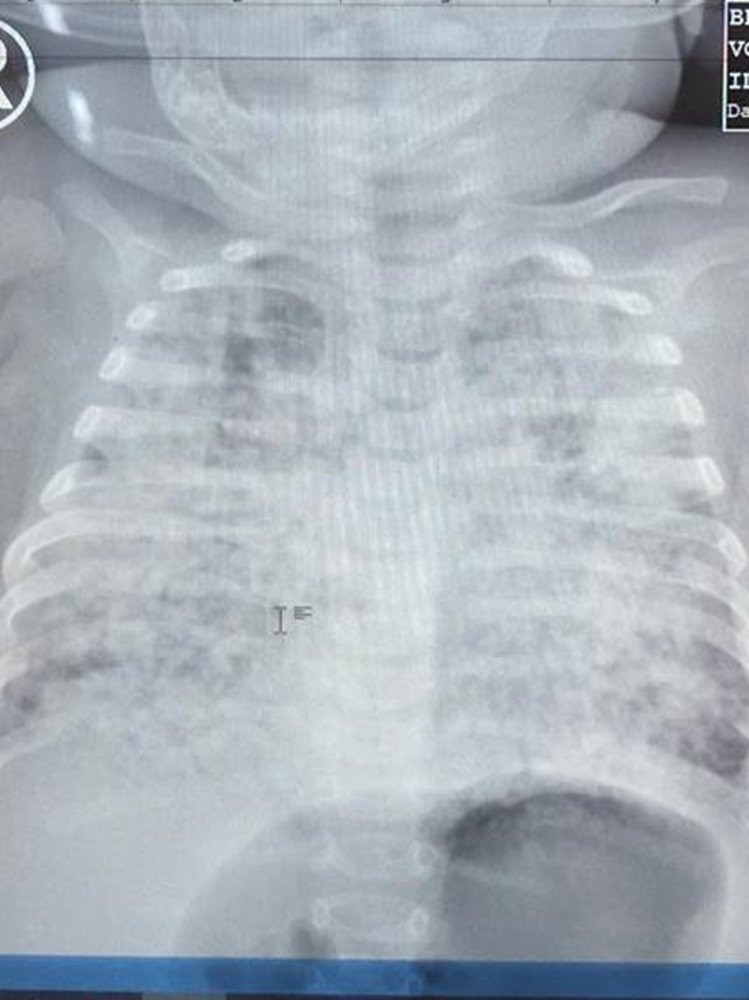

Phổi bé trai trắng xóa.

Tại đây, phổi bé đã trắng xoá, xét nghiệm mới biết nhiễm lao kê rất nặng. Kể từ ngày đó, chị N. thấp thỏm khi bệnh tình con chưa cải thiện được bao nhiêu lại trở nặng. Căn bệnh lao kê diễn tiến phức tạp, tàn phá phổi bé ghê gớm.

Bệnh nhi được điều trị kháng sinh và kháng lao tấn công hơn gần 3 tháng theo phác đồ... Nhờ được theo dõi điều trị tích cực, phổi bé sáng dần lên, mô phổi giảm tổn thương và thông khí ngày càng hiệu quả, các kén khí lớn giảm rõ rệt.

Sau 3 tháng, bé dần hồi phục.